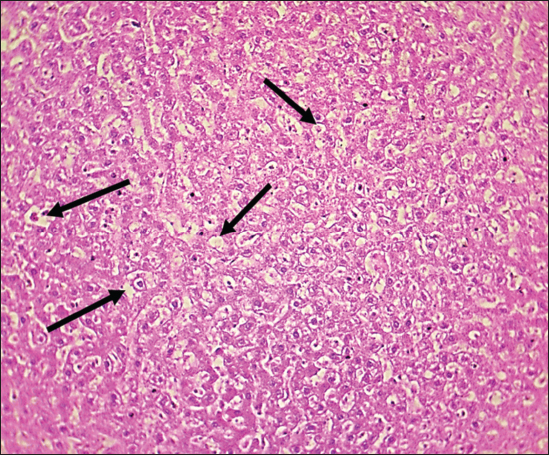

Fig. 7. Histological section of the liver of rats drenched with 0.6 mg/kg citalopram. The section shows clear hepatic vein congestion (black arrows) narrowing of the hepatic artery and arteriole diameter (red arrows) (H and E stain 400X).

Fig. 8. The histopathological section in the liver of rats drenched with 0.6 mg/kg citalopram. The section shows fat droplet accumulation in hepatocytes (fatty liver, black arrows) (H and E stain 100X).

The results of this study revealed no significant differences in bilirubin levels in all treated animals (Table 1), whereas serum ALT and AST levels showed significant elevations in all treated animals either by citalopram alone (fourth group) or with J. regia pulp extract at doses of both 10 and 20 mg/kg (Tables 2 and 3). Sections of histopathological study appeared as mild degenerative lesions characterized by infiltration of fat droplets inside hepatic cells, which gave them a ring shape appearance due to pushing the nucleus at one side from the hepatic cells with fibrous networks formation in the tissue parenchyma, infiltration of structureless, homogenous, and pinkish material (Figs. 16). Clear hepatic vein congestion and narrowing in the hepatic artery and arteriole diameters revealed that citalopram caused liver dysfunction and injury (Figs. 79).

These results correspond with those of other studies, in which patients treated with antidepressants appeared to have moderately elevated levels of the aminotransferase. All antidepressants caused hepatotoxicity; citalopram is that have the least potential for hepatotoxicity, which is characterized by high alanine aminotransferase levels (Gartlehner et al., 2008; Voican et al., 2014; Ilgın et al., 2020). The results of this study revealed no significant differences in bilirubin levels in all treated animals as the level of p < 0.05, serum ALT and AST levels showed a significant elevation in all treated animals either by citalopram only (fourth group) or with J. regia pulp extract at doses of 10 and 20 mg/kg B.W. Sections of histopathological sections show mild degenerative lesions characterized by infiltration of fat droplets inside hepatic cells, which give them a ring shape appearance due to pushing the nucleus at one side from the hepatic cells with fibrous networks formation in the tissue parenchyma, infiltration of structureless, homogenous, and pinkish material (Figs. 4 and 6). Clear hepatic vein congestion and narrowing in the hepatic artery and arteriole diameters revealed that citalopram caused liver dysfunction and injury (Figs. 79).